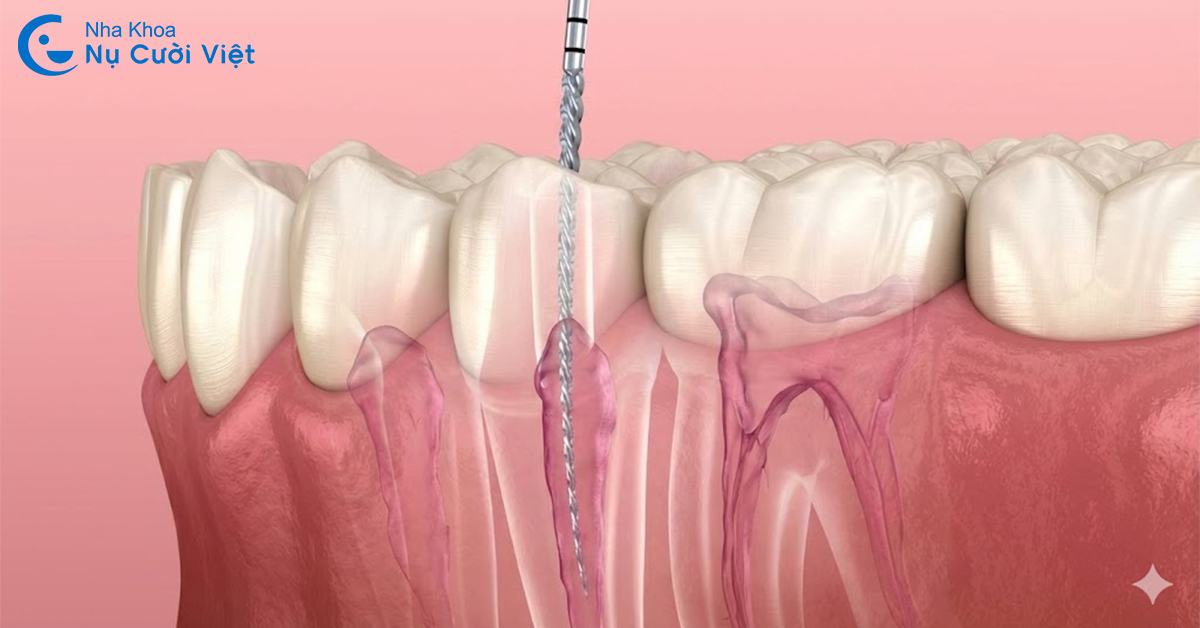

Lấy tủy răng (hay còn gọi là điều trị nội nha) là quy trình lấy sạch toàn bộ phần tủy răng bị tổn thương (cả tủy buồng và tủy chân). Sau đó trám kín lại ống chứa tủy và phục hồi răng để tránh nhổ bỏ răng. Trong các trường hợp viêm tủy không hồi phục hoặc tủy đã hoại tử, việc lấy tủy răng (chữa tủy) là chỉ định bắt buộc. Ngược lại, nếu tình trạng tổn thương tủy răng không cấp thiết thì không bắt buộc phải lấy tủy răng.

Do cấu trúc ống tủy phức tạp, cong, hẹp hoặc có nhiều nhánh phụ, nếu bác sĩ không làm sạch và tạo hình ống tủy đúng chuẩn, vi khuẩn sẽ tiếp tục tồn tại và phát triển âm thầm.

Hậu quả là người bệnh có thể gặp tình trạng đau tái phát sau khi đã chữa tủy, nướu sưng, đau khi cắn hoặc xuất hiện ổ viêm quanh chóp răng. Trường hợp nặng hơn có thể hình thành áp xe, tiêu xương ổ răng và buộc phải điều trị lại hoặc nhổ răng nếu viêm nhiễm lan rộng.

Viêm quanh cuống răng do nhiễm khuẩn từ tủy răng